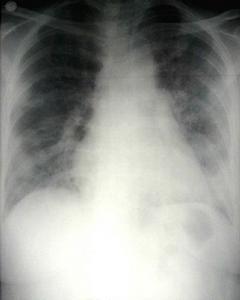

乳汁吸入性肺炎發紺2 呼吸系統症狀和體徵 嚴重度與吸入的量與次數有關。吸入量少或偶然吸入者以支氣管炎為主,症狀有咳、喘、氣促。吸入量多時發生肺炎 一次大量吸入,可引起窒息,呼吸停止至呼吸恢復後,出現明顯氣促,肺部羅音多。長期多次吸入者發生音質性肺炎,最後導致肺纖維化或並發支氣管擴張症。